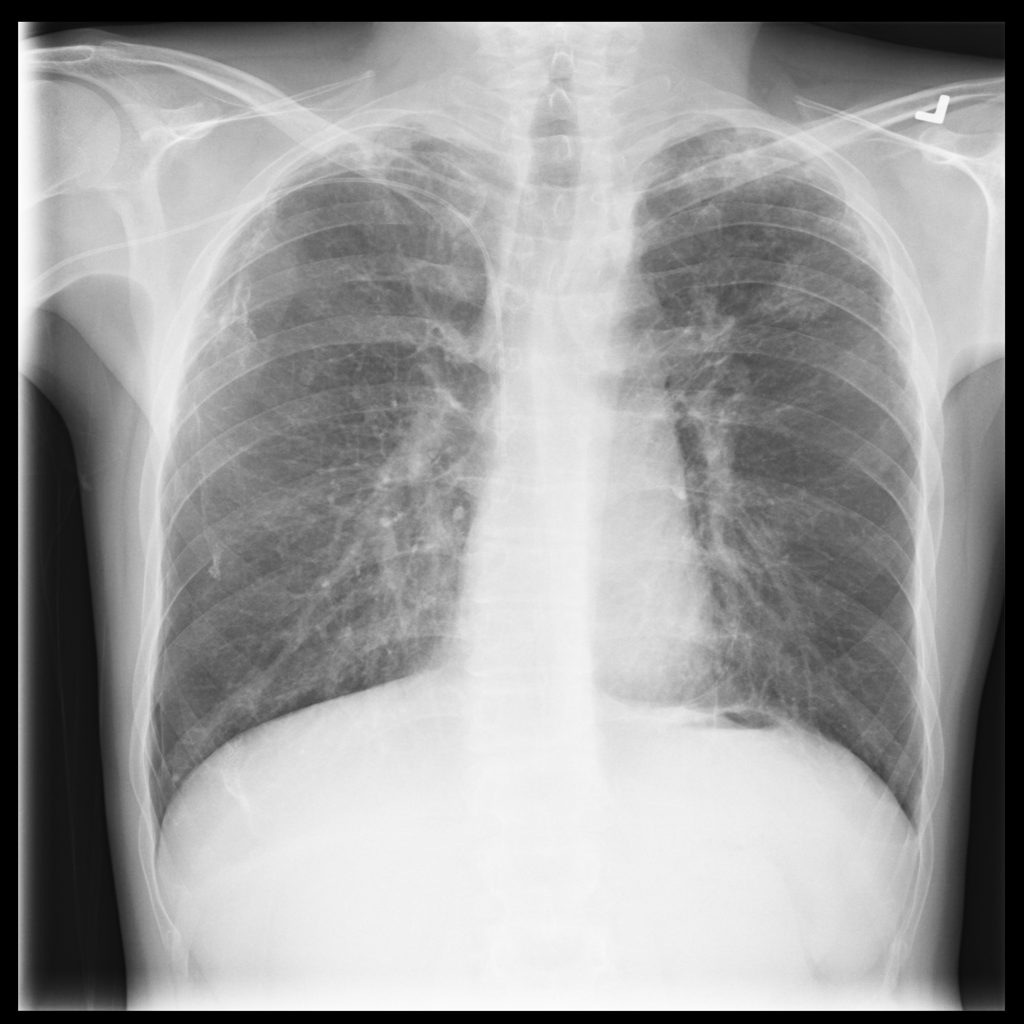

Showing up to 90 reference images for Pneumothorax.

PAT-4639 · IMG-013Pneumothorax

PAT-4639 · IMG-013

AP